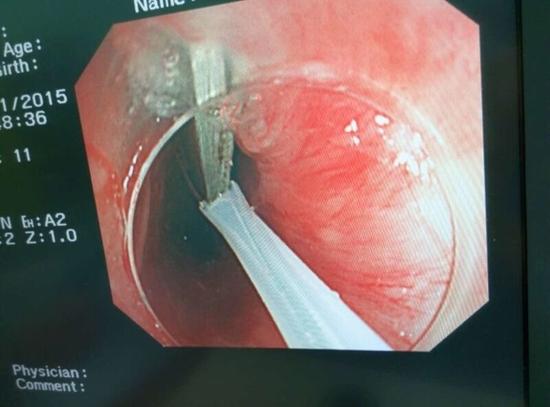

醫(yī)生從華先生胃里取出的鑷子和打火機(jī)

手術(shù)中,范醫(yī)生通過胃鏡準(zhǔn)確發(fā)現(xiàn)了胃里的鑷子。但讓他驚訝的是,在華先生胃底竟然還躺著三個被腐蝕了的打火機(jī),打火機(jī)的金屬部件都已經(jīng)不見了。

隨后,范醫(yī)生先用圈套器套取出了長10厘米的鑷子,再一個一個地取出了打火機(jī)。整個取出過程小心謹(jǐn)慎而又一氣呵成,只用了不到10分鐘。